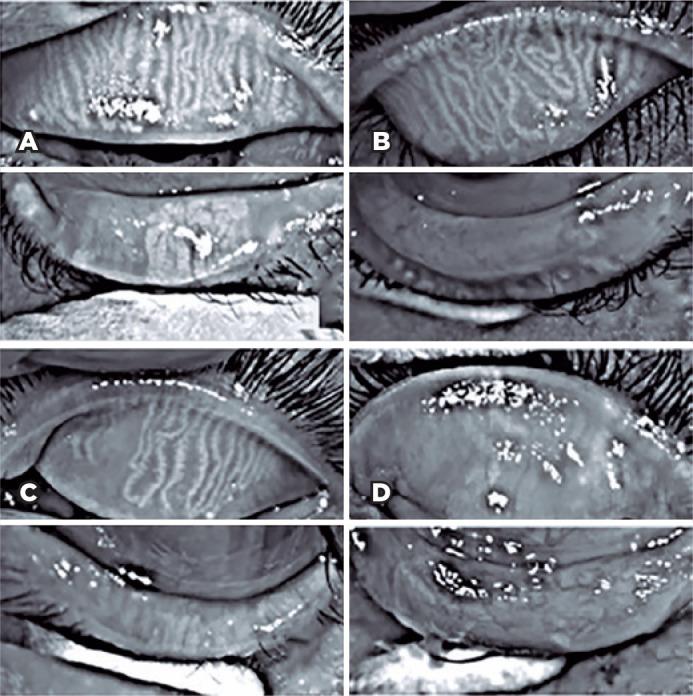

To assess Meibomian gland dysfunction using meibography in patients with xeroderma pigmentosum and correlate with ocular surface changes.

This cross-sectional study evaluated patients with xeroderma pigmentosum. All patients underwent a comprehensive and standardized interview. The best-corrected visual acuity of each eye was determined. Detailed ophthalmic examination was conducted, including biomicroscopy examination of the ocular surface, Schirmer test type I, and meibography, and fundus examination was also performed when possible. Meibomian gland dysfunction was assessed by non-contact meibography using Oculus Keratograph® 5M (OCULUS Inc., Arlington, WA, USA). Saliva samples were collected using the Oragene DNA Self-collection kit (DNA Genotek Inc., Ottawa, Canada), and DNA was extracted as recommended by the manufacturer. Factors associated with abnormal meiboscores were assessed using generalized estimating equation models.

RESULTS

A total of 42 participants were enrolled, and 27 patients underwent meibography. The meiboscore was abnormal in the upper eyelid in 8 (29.6%) patients and in the lower eyelid in 17 (62.9%). The likelihood of having abnormal meiboscores in the lower eyelid was 16.3 times greater than that in the upper eyelid. In the final multivariate model, age (p=0.001), mutation profile (p=0.006), and presence of ocular surface malignant tumor (OSMT) (p=0.014) remained significant for abnormal meiboscores. For a 1-year increase in age, the likelihood of abnormal meiboscores increased by 12%. Eyes with OSMT were 58.8 times more likely to have abnormal meiboscores than eyes without ocular surface malignant tumor.

CONCLUSION

In the final model, age, xeroderma pigmentosum profile, previous cancer, and clinical alterations on the eyelid correlated with a meiboscore of ≥2. Meibomian gland dysfunction was common in patients with xeroderma pigmentosum, mainly in the lower eyelid. The severity of Meibomian gland dysfunction increases with age and is associated with severe eyelid changes.